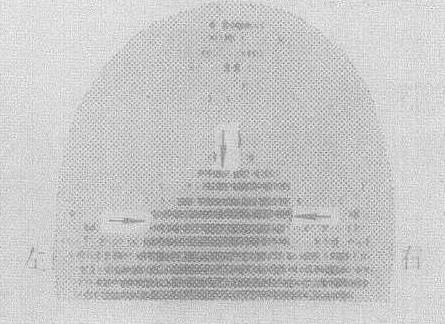

❺169Yb-DTPA静脉注射后24小时内即可从肾脏排出99%,目前已被重视,逐渐广泛采用(图3ab)。特别用做脑池,脑室造影,观察脑脊髓液的动态变化,诊断幕下和颅底病变,因毒性小,图像显示清晰,比较理想。

图3a 后前位,右颞顶枕脑膜瘤160Yb-DTPA 10mCi

图3b 右侧位